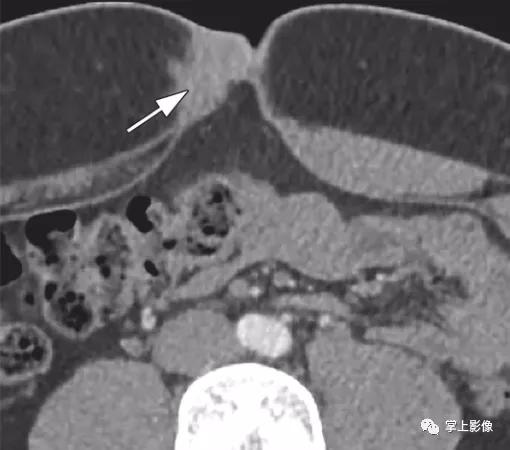

45岁男性血管瘤。轴位平扫CT示长形含脂肪肿块(白色箭头),左侧外斜肌和内斜肌之间数枚钙化静脉石(黑色箭头)。这些发现是腹壁肌肉内血管瘤的特征